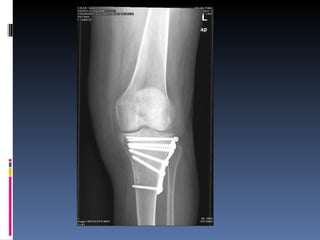

Osteoartritis IFDs, IFPs, 1 st  CMC Osteofitos Estrechez asimetrica del espacio articular  Esclerosis subcondral Quistes subcondrales No erosiones marginales Densidad osea preservada

Osteoartritis

Osteoartritis IFDs, IFPs,1 st CMC Osteofitos Estrechez asimetrica del espacio articular Esclerosis subcondral Quistes subcondrales No erosiones marginales Densidad osea preservada